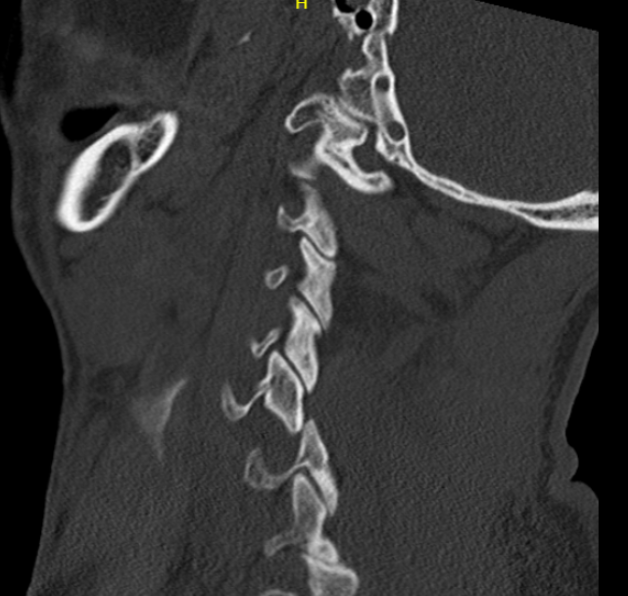

Bilateral jumped facets on CT